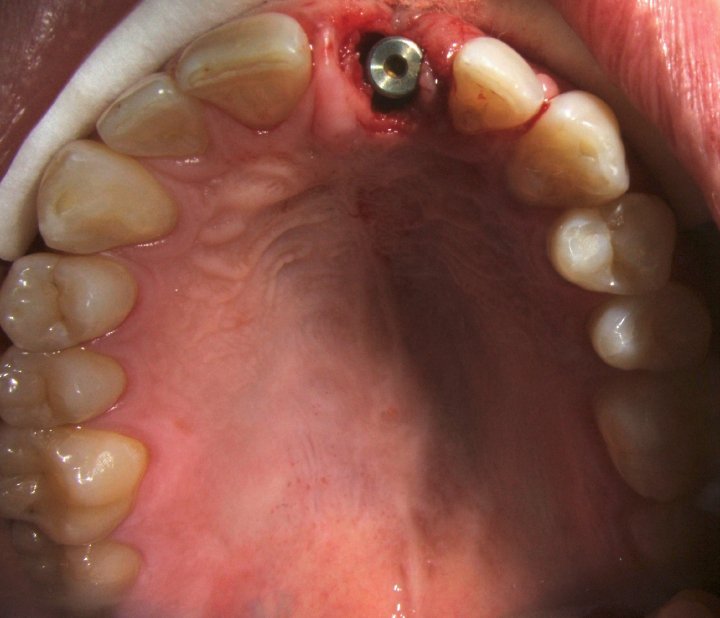

Healing Screw On The Impant

Immediate Implant Placement